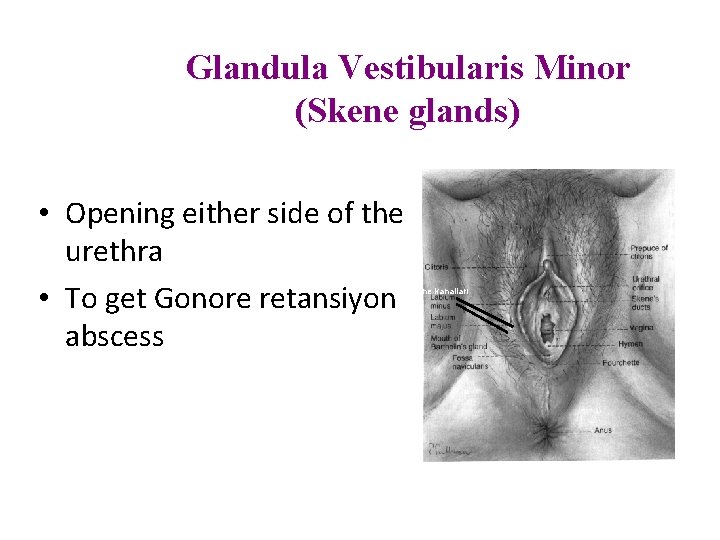

Glandula Vestibularis Minor (Skene glands) • Opening either side of the urethra • To get Gonore retansiyon abscess Skene kanalları